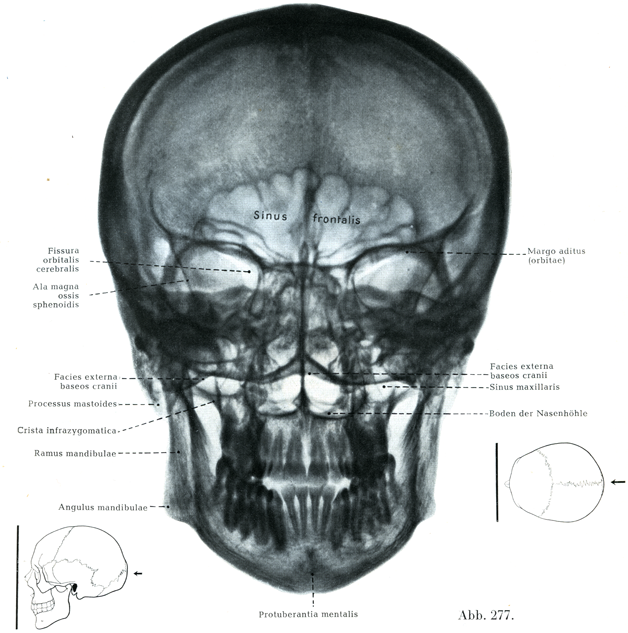

[図277]さらした頭蓋のレントゲン像 背腹照射(7/10)